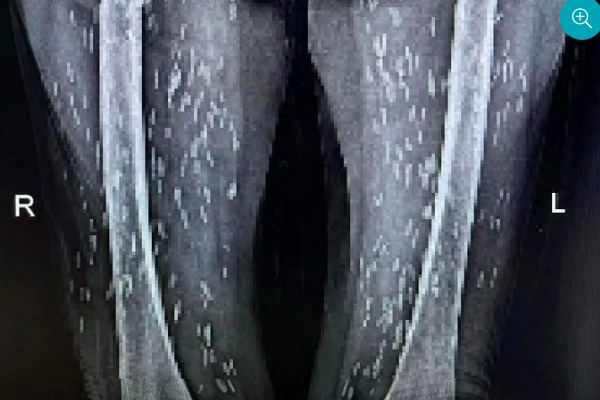

Các bác sĩ đã chỉ định cho bệnh nhân thực hiện chụp X- quang thường quy. Kết quả phát hiện thấy hình ảnh nhiều kén sán hình dạng kích cỡ như hạt gạo nằm rải rác trong các mô, cơ trên phim trường vùng ngực, khi kiểm tra thêm vùng bụng, hai chi dưới phát hiện thấy rất nhiều kén sán mật độ dày toàn bộ cơ thể.

Bệnh nhân choáng váng khi các bác sĩ chẩn đoán bà bị nhiễm kén sán dây lợn. Những nang kén này có thể đã tồn tại trong cơ thể người bệnh từ 5 đến 7 năm.

Hình ảnh kén sán trắng như hạt gạo dày đặc trên người bệnh nhân